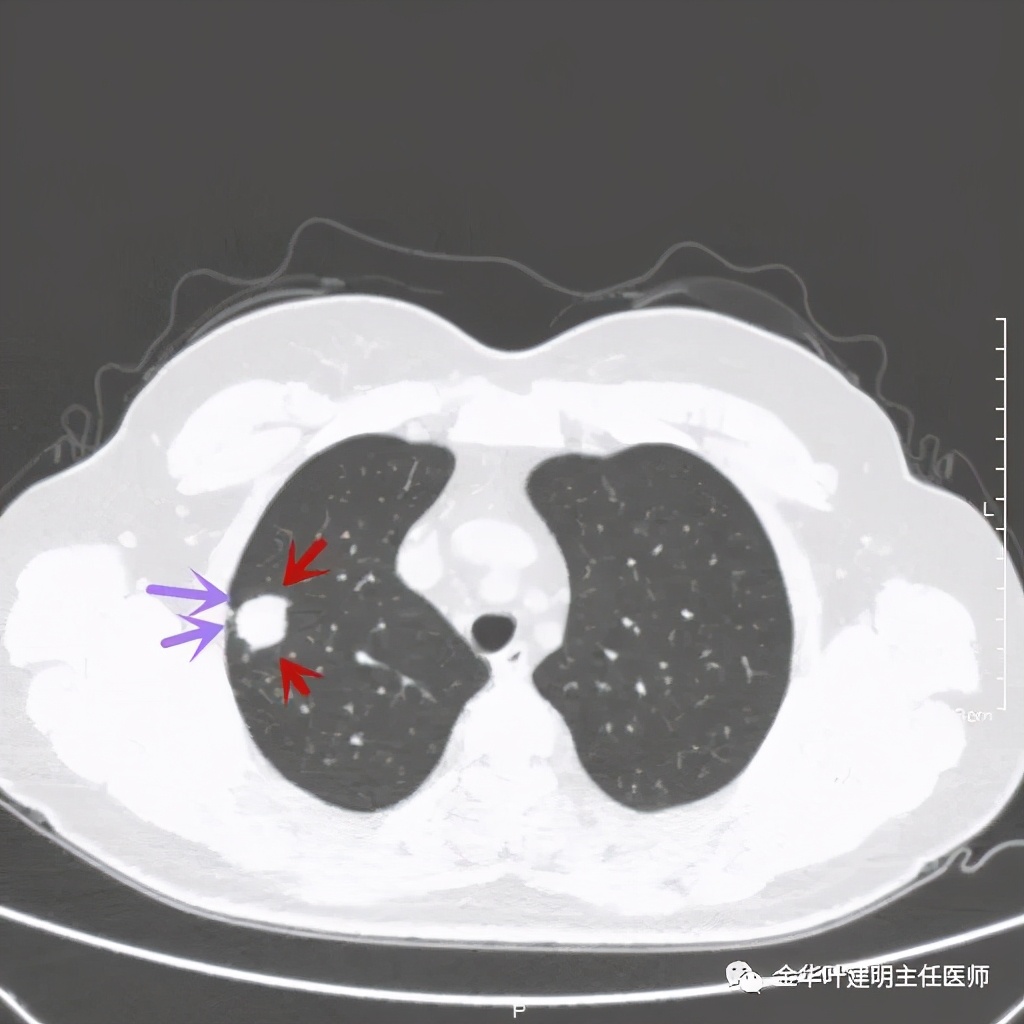

右上叶开始出现病灶,是实性的

病灶比较光滑,密度高,旁边有小的卫星灶,不清爽

紫色箭头示病灶与胸膜很近,但无牵拉凹陷,绿色箭头示附近有微小其他病灶